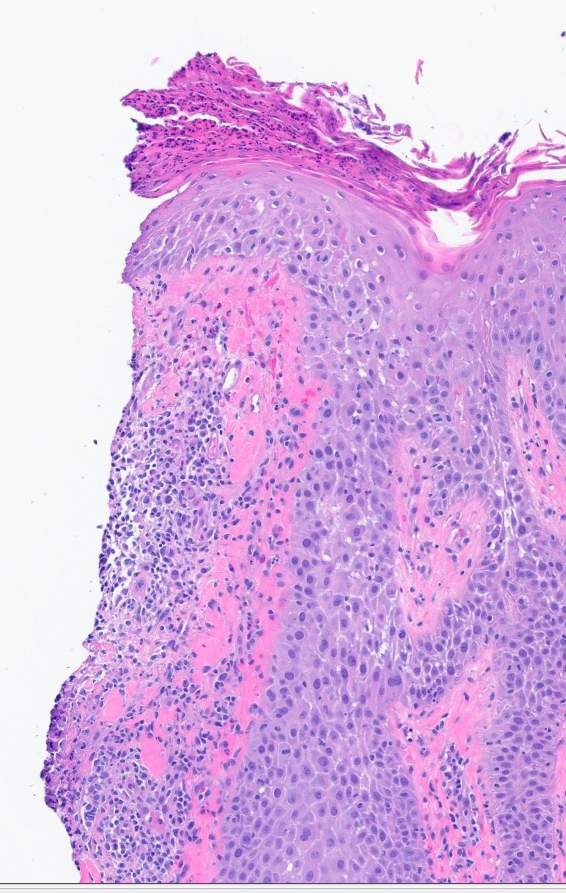

I'm so honored to receive the Dermatopathology Trainee World Cup 1st place for my presentation on cysts mimicking malignancies with Drs. Foulis and Gibbs! Had a great time, learned a lot, and met many amazing people @IntSocDermpath #ISDP2023 #PathTwitter #dermpath #dermtwitter